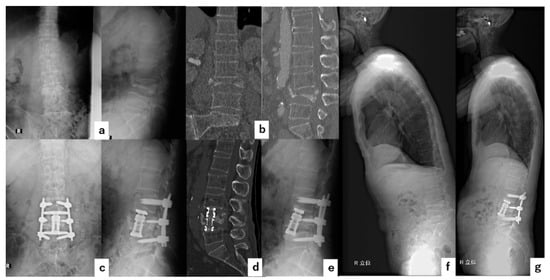

4.2. Case 2